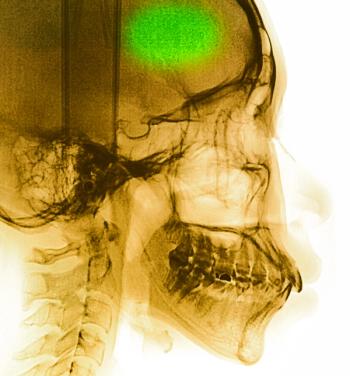

Creutzfeldt-Jacob disease should be considered in the setting of a rapidly progressive dementia with psychiatric symptoms, ataxia, mutism, myoclonus, and pyramidal or extrapyramidal signs.